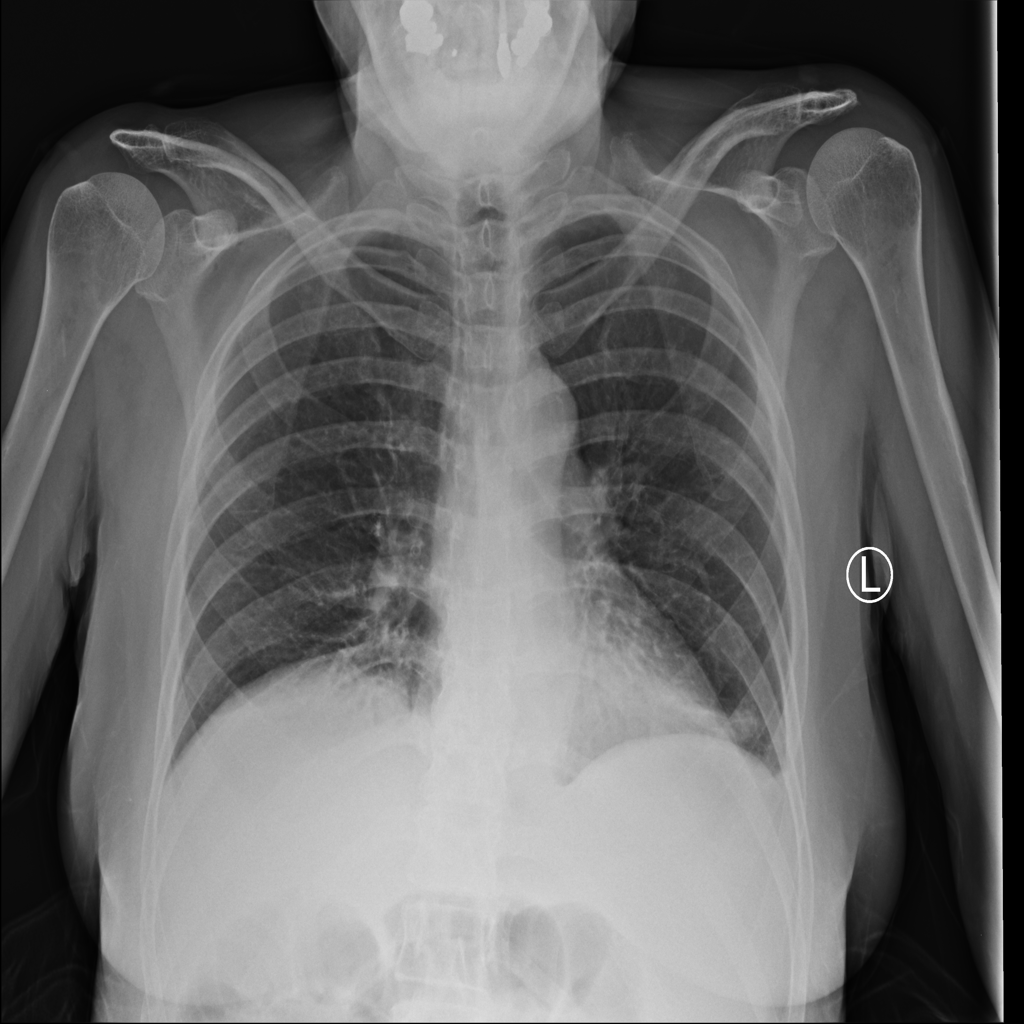

PAT-DB80 · IMG-000Atelectasis

PAT-DB80 · IMG-000

PA